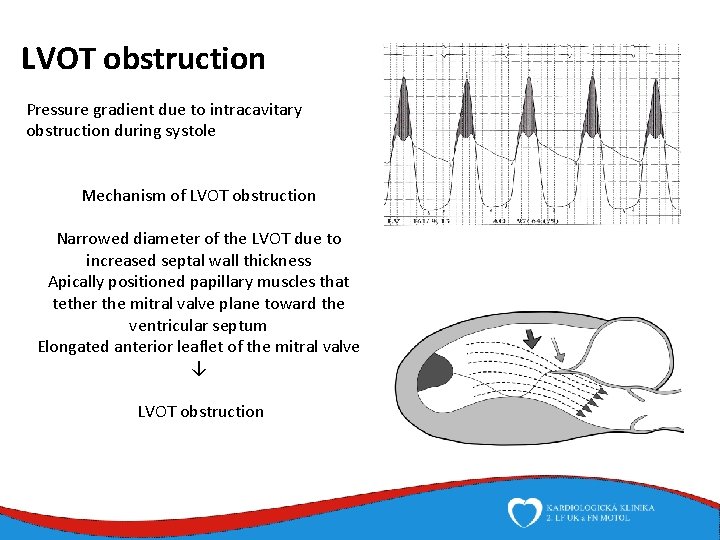

LVOT obstruction Pressure gradient due to intracavitary obstruction during systole Mechanism of LVOT obstruction Narrowed diameter of the LVOT due to increased septal wall thickness Apically positioned papillary muscles that tether the mitral valve plane toward the ventricular septum Elongated anterior leaflet of the mitral valve ↓ LVOT obstruction